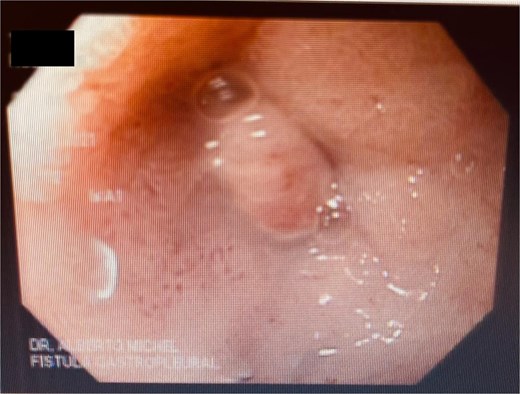

A 44-year-old female with no significant medical history underwent Roux-en-Y gastric bypass for grade III obesity (BMI 41). She presented with necrosis of the gastric pouch within the first 48 hours, leading to leakage of the gastrojejunal and jejunojejunal anastomoses. Esophagojejunal anastomosis and revision of the jejunojejunal anastomosis were performed, but the patient developed septic shock due to esophagojejunal anastomosis leakage, requiring 7 days in intensive care. Upon stabilization, she was referred to our service for endoscopic management of an esophagojejunal fistula. A 10 mm fistulous orifice was observed (Fig. 1), and EVAC therapy was initiated using a polyurethane sponge with an 8 Fr catheter at 125 mmHg continuous suction (Fig. 2). Six changes were made at 3–5-day intervals.

The placement of the catheter and sponge for EVAC therapy is observed.